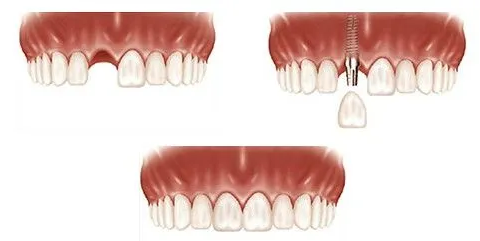

医生和我们说有两种方案可以选择,一个是价格便宜的活动义齿,平时也方便摘戴。还有一种是价格比较贵一点的种植牙,虽然会贵一些,但是无论是看上去还是用起来都和原来的真牙相信。

经过我们一家人讨论,也是听了爸爸的建议,宁愿多花一点钱也不能让爷爷以后在牙齿上再出什么大问题。于是我们就选了做种植牙的方案,但是因为爷爷原先牙周就有问题,先把牙周问题治疗好了以后,才做种植牙。